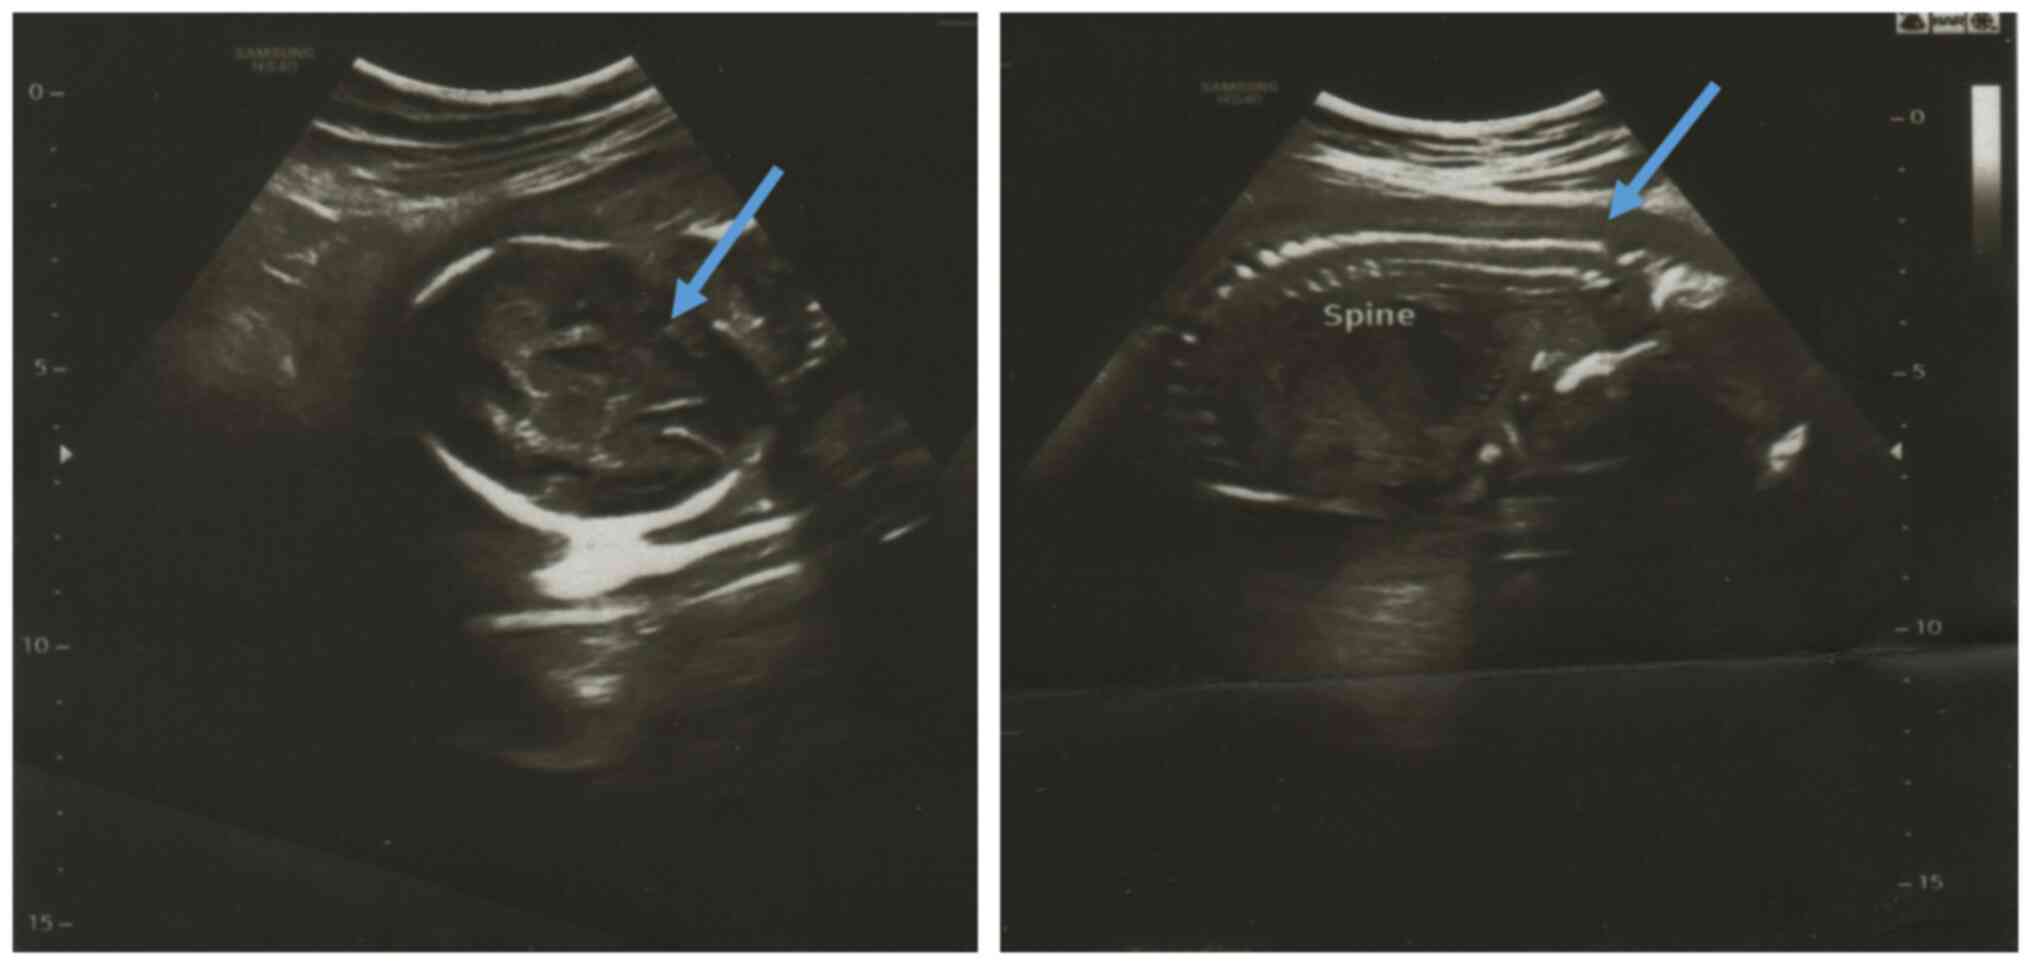

Missense mutation (Ser654Leu) in the ITGA8 gene associated with renal hypodysplasia: A case report

Renal hypodysplasia is a congenital kidney anomaly that occurs when part of the kidney does not fully develop in the womb. Numerous genes have been identified that when mutated, result in renal dysplasia. This has encouraged the authors to search for additional genes and variants potentially linked to renal anomalies. Using next‑generation sequencing combined with Sanger sequencing, a missense variant in the ITGA8 gene (NM_003638.2:c.1961C>T; p.Ser654Leu) associated with renal hypodysplasia was identified. Detailed studies on this variant revealed that Ser654 is conserved across species, and the mutation is located in the extracellular domain of the protein, which plays an essential role in ligand binding and protein‑protein interactions. This is the first study presenting the clinical correlation of the ITGA8 variant (Ser654Leu) with renal hypodysplasia.